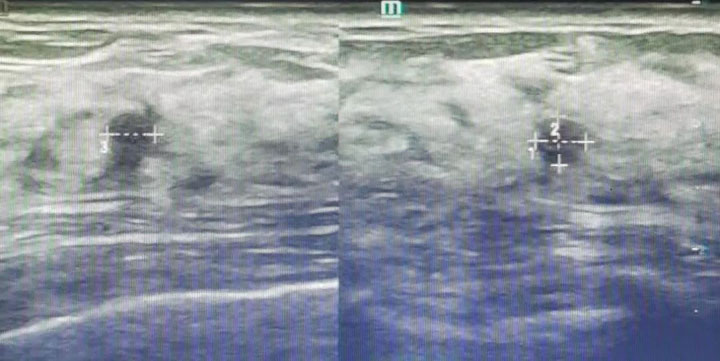

据了解,张女士的乳腺彩超检查提示:双侧乳腺多发结节(BI-RADS:3类);双乳多发囊肿(BI-RADS:2类),诊断为乳房多发纤维瘤。综合评估后,科室为其顺利在超声下行乳房包块微创旋切术。“病理是良性的,和医生判断的一样,我现在放心了。术后伤口和针眼差不多,几乎看不到。很满意。”术后第二天,张女士恢复良好回家继续休养,不久,她便送来锦旗表达谢意。

科主任顾冕介绍,2013年东方医院集团总院甲乳外科在本市率先开展美国安珂乳腺微创旋切技术,每年开展300余例。广济医院开诊后,很快将这项微创技术带来西部地区。相较于常规手术,该术定位准确、创伤小、恢复快,术后伤口仅5mm左右,可以做到无手术疤痕,让更多乳腺良性结节的患者,尤其年轻女患者重拾健康与自信,彻底摆脱癌变的阴影。